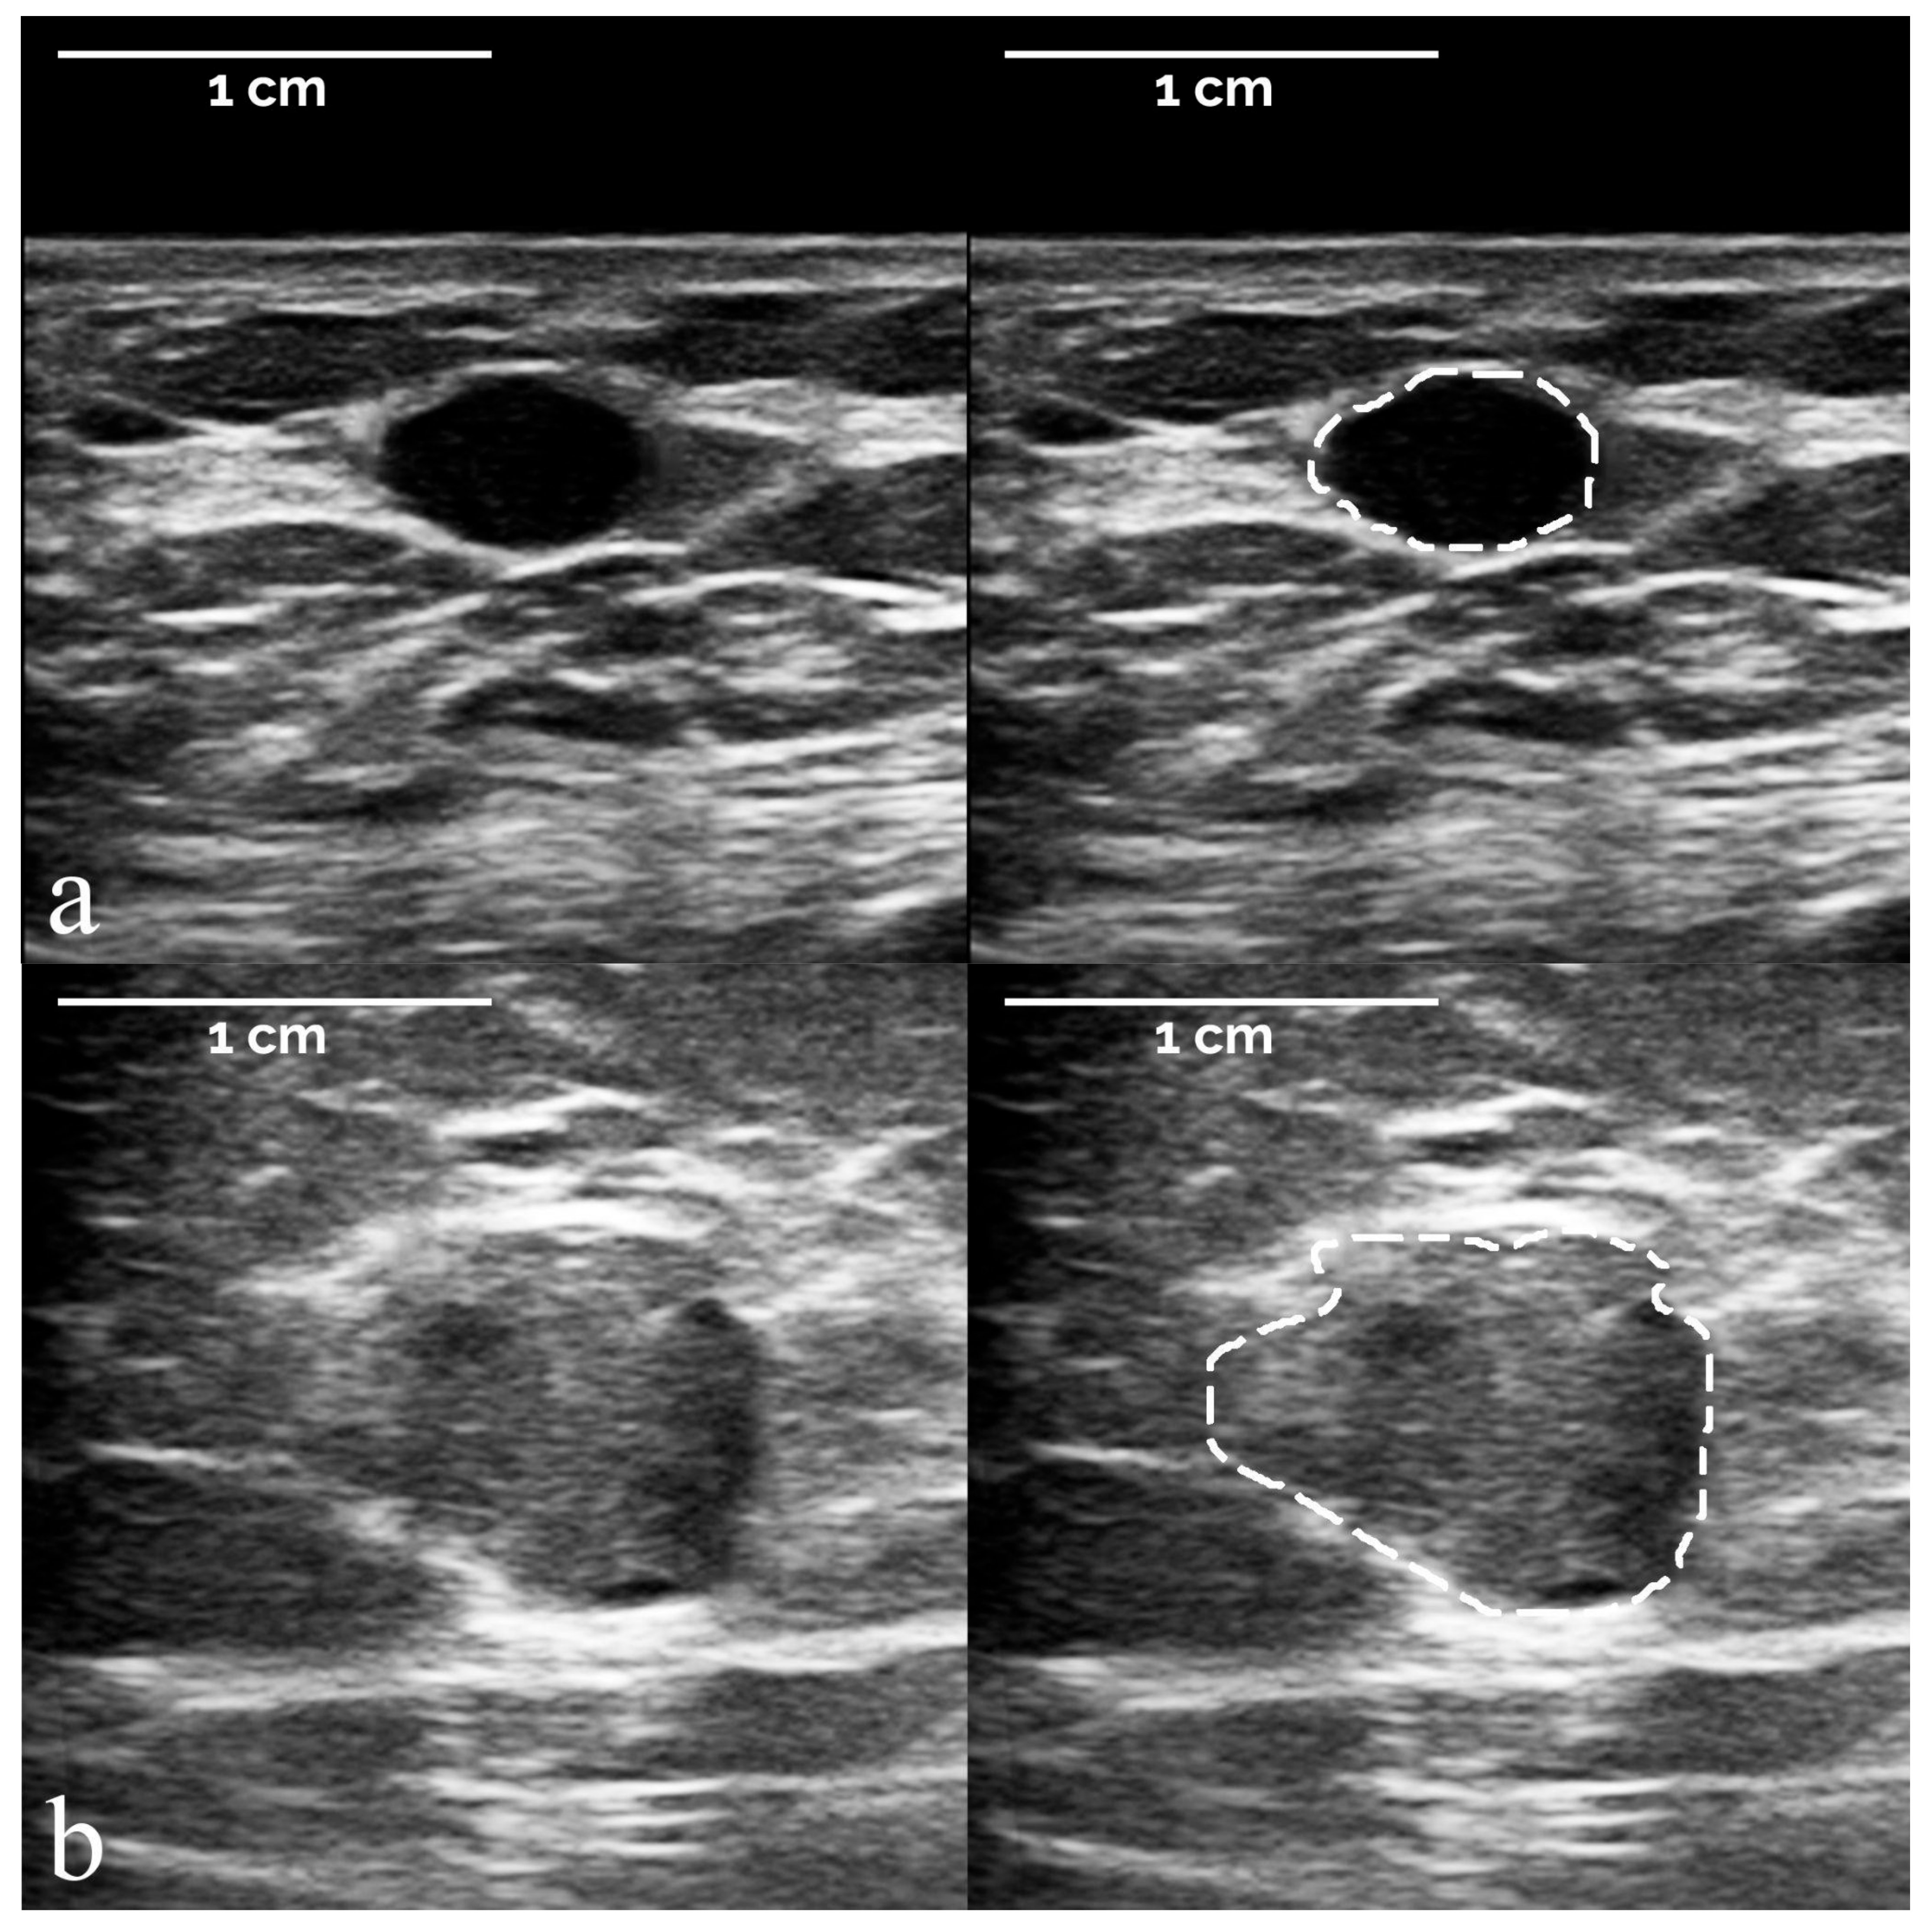

- The segmentation of suspicious masses on all 821 images was performed manually by a board-certified radiologist with 34 years of experience in breast imaging, using the TRACE4 segmentation tool. The same radiologist (at a time distance of 8 weeks) and a second board-certified radiologist with 7 years of experience independently segmented the masses on a random subsample of 50 images from the training dataset, fully blinded to histopathology and other segmentations.